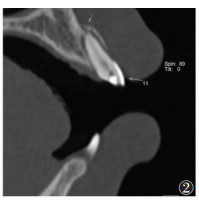

2 结果28例共49颗牙齿根折(图 1),其中单颗牙根折18例(64.3%),多颗牙根折10例(35.7%);中切牙根折39颗(79.6%),侧切牙根折10颗(20.4%);8例合并冠折;9例合并邻近牙槽突骨折;10例合并邻牙损伤,其中6例为牙齿缺如,4例为冠折(图 2,3)。49颗根折牙齿中,骨折线位于根颈1/3处12颗(24.5%),根中1/3处6颗(12.2%),根尖1/3处31颗(63.3%),以根尖1/3处最常见(图 4,5)。

| 图 3 男,40岁 图3a,3b MIP及VR清晰显示11~12牙邻近牙槽突骨折情况(箭头) |